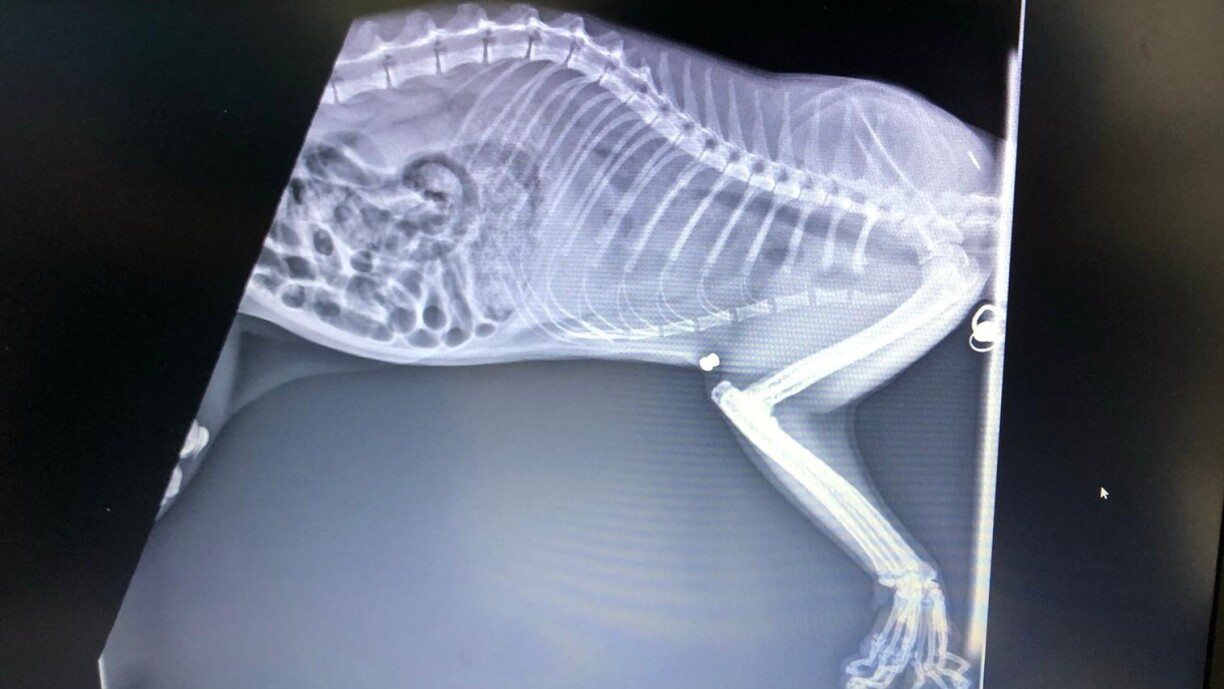

In the morning she brought him to the vet, who, following an autopsy and X-ray, made a shocking discovery: an air gun bullet had pierced Paolino's back, damaging vital organs.